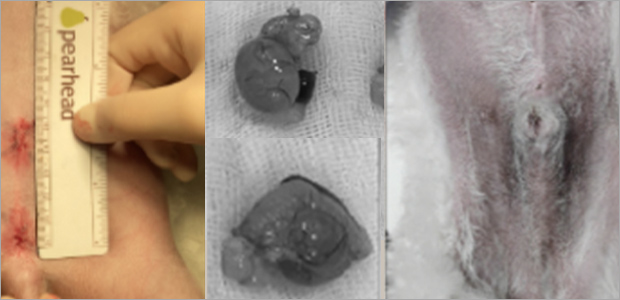

복강경 남아 잠복고환 수술

남아 잠복고환의 경우에도 전체 개복을 하지않고 최소절대 복강경 수술을 통해

복강경 카메라로 잠복고환을 찾고 기구 포트를 통해 제거합니다.

케이스1

- 수술 직후

- 제거된 잠복고환

- 수술 2주차

담낭점액종 수술

담낭점액종은 병기가 진행되어 담도폐색 및 담낭파열이 발생할 수 있는 질환입니다.

이는 사망에 이를 수 있는 위험한 응급상황이기에, 적절한 시기에 수술 계획을 세우고

수의사 상담을 통해 개복 또는 복강경을 사용한 담낭절제술을 진행합니다.

담낭점액종으로 인한 응급상황(폐색, 파열) 발생 후 절제 수술한 경우보다 조기에 담낭절제수술을 한 경우 확연히 좋은 예후를 보여줍니다.

그렇기 때문에 후 응급 상황이 발생하기 전에 선제적 담낭절제술을 진행하는 것에 대해 고민해봐야 합니다.

담도폐색 환자 개복담낭절제술 케이스